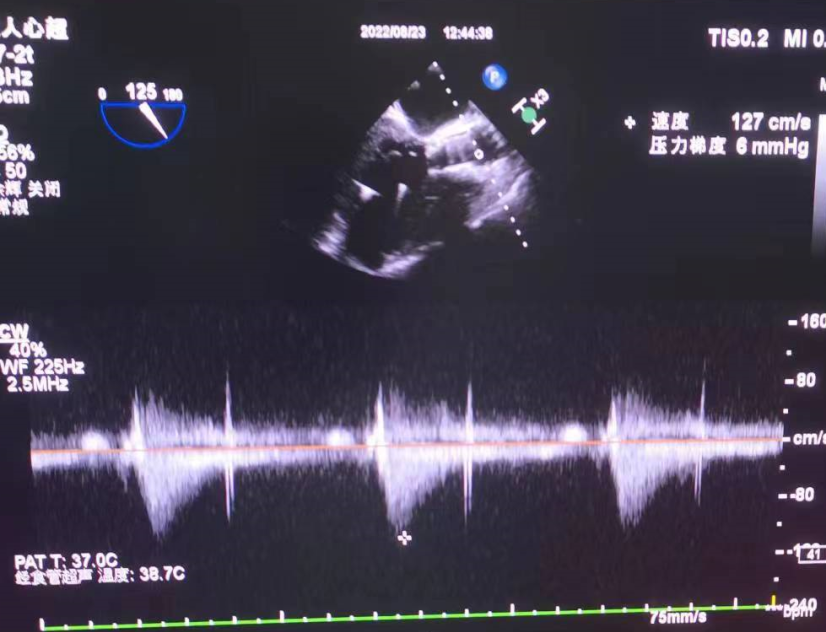

超声看位置合适,无反流

患者压差从64mmHg降为4mmHg,效果显著。

患者压差从163mmHg降为6mmHg,效果显著。